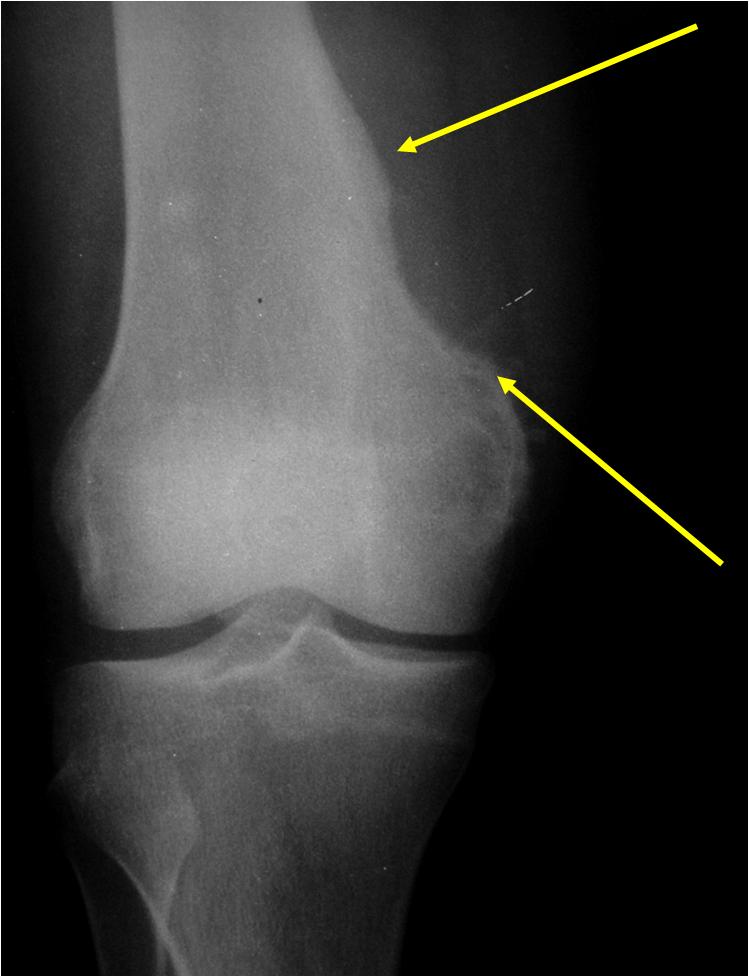

Radiology:

- Metaphyseal

- Cortical erosion with sclerotic underlying cortex (saucer shaped defect)

- Matrix calcification

- Triangular sclerotic spur at margin of tumor

- >5cm in diameter; average size: 11 cm (vs periosteal chondroma that is usually <5cm)

- No hair on end periosteal reaction (vs. chondroblastic osteosarcoma)

- Intramedullary canal is spared

(Bottom Arrow) Erosion of Outer Cortex